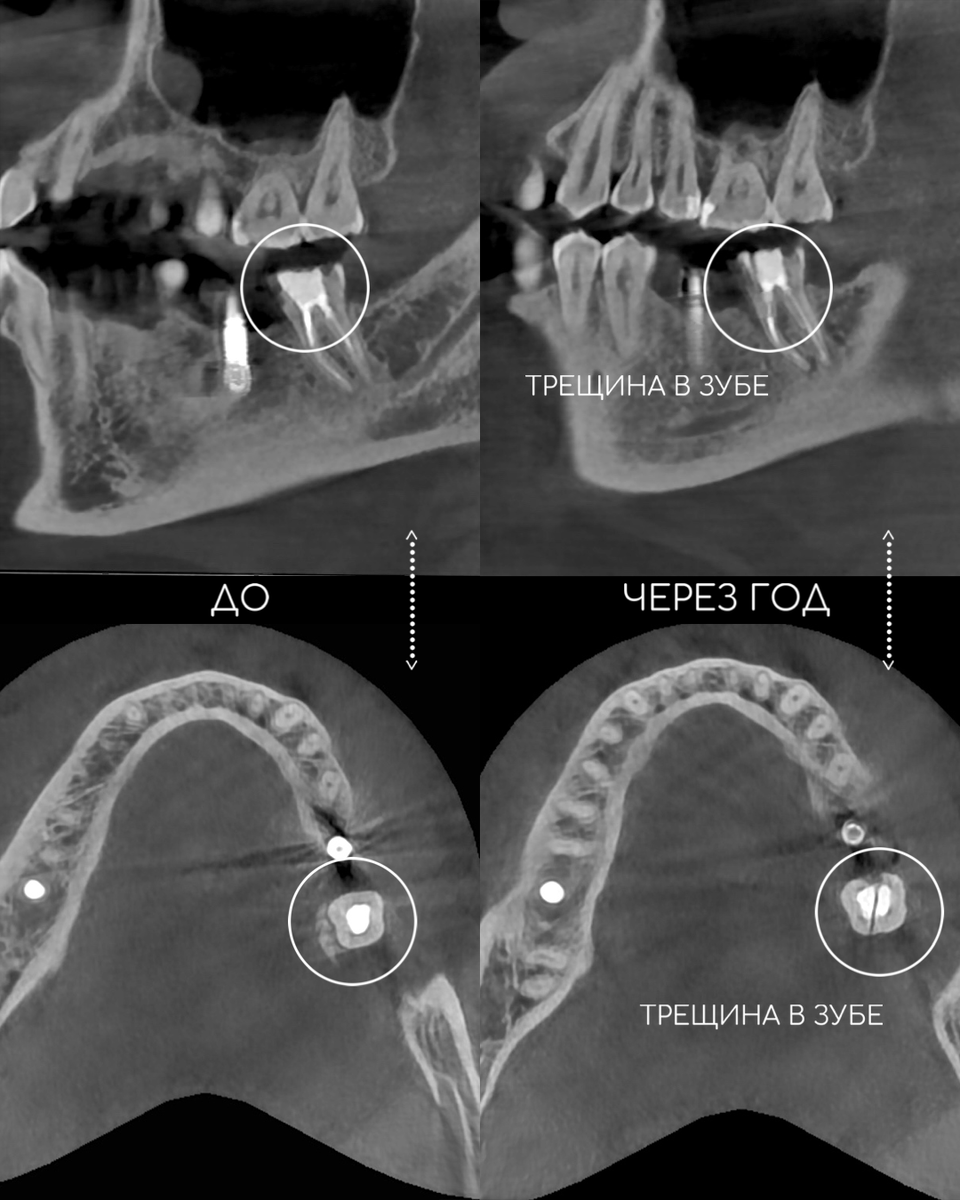

Зуб треснул..

Закончу прозой: если зуб сильно разрушен (тем более, когда зуб без нерва), то коронку придется ставить в любом случае. Будет ли она на своём зубе или на импланте, решаете вы 🙌🏼